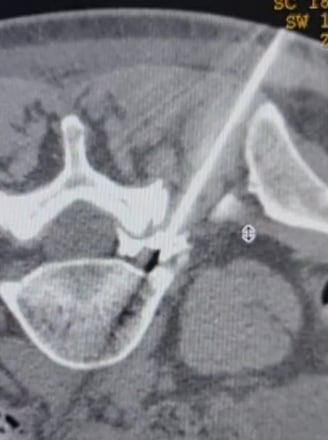

Biópsias Guiadas por Imagem (TC,USG ou Fluoroscopia)

Retirada de um fragmento de tecido vivo para determinação de um diagnóstico. Este procedimento é utilizado para inúmeras ocasiões na prática médica, como por exemplo para definir o diagnóstico de um tumor, determinar o seu tipo histológico e agressividade, documentar a existência de lesões metastáticas ou até mesmo para determinar a natureza de uma lesão (neoplásica ou infecciosa).